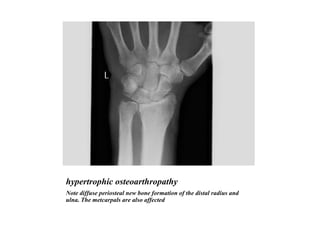

hypertrophic osteoarthropathy Note diffuse periosteal new bone formation of the distal radius and ulna. The metcarpals are also affected

hypertrophic osteoarthropathy Notediffuse periosteal new bone formation of the distal radius and ulna. The metcarpals are also affected